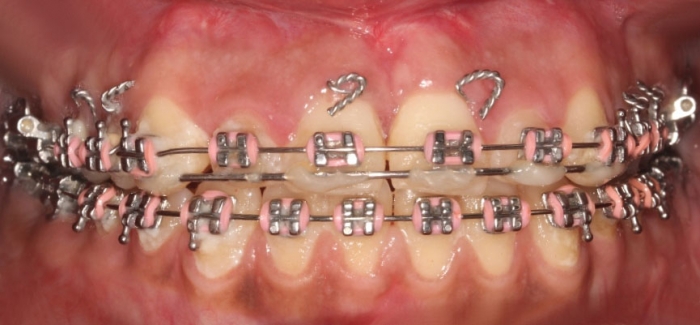

Mordida após a cirurgia  - Clínica Cliniface

Mordida após a cirurgia